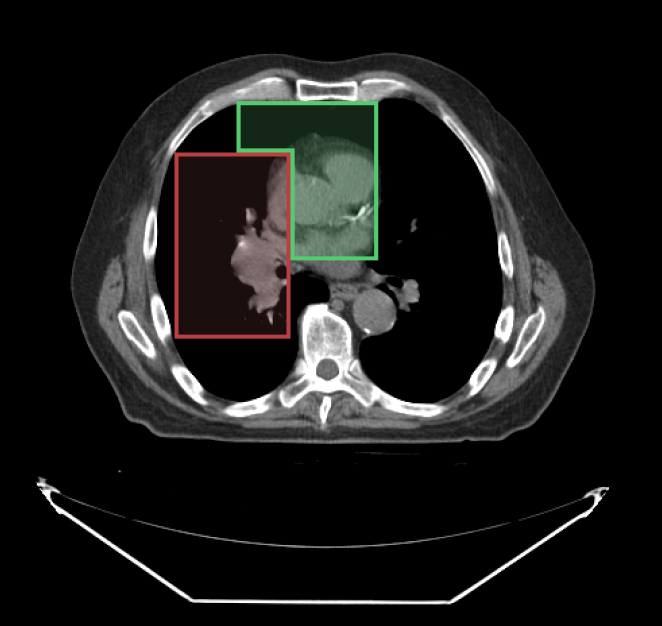

When drawing with segmentation tools, you can specify which segment index to use. Below, we have used the SegmentIndex API to change the segmentIndex to draw the second segment.